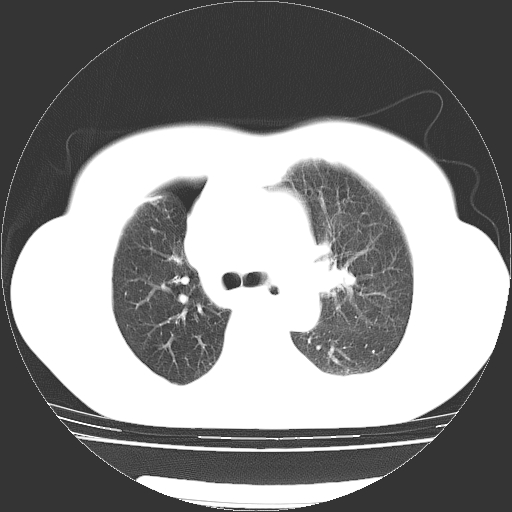

以下是引用zhangzhongshou在2008-3-22 12:52:00的发言:[br]1、右侧液气胸。[br]2、腹水。建议进一步检查。

以下是引用鲁巨ct在2008-3-22 14:10:00的发言:[br]1、右侧液气胸,右中下叶节段性不张。[br]2、腹水,建议上腹部ct检查

以下是引用zjzjr在2008-3-22 17:19:00的发言:[br]1、右侧液气胸,右下叶节段性不张。[br]2、腹水,建议上腹部ct检查